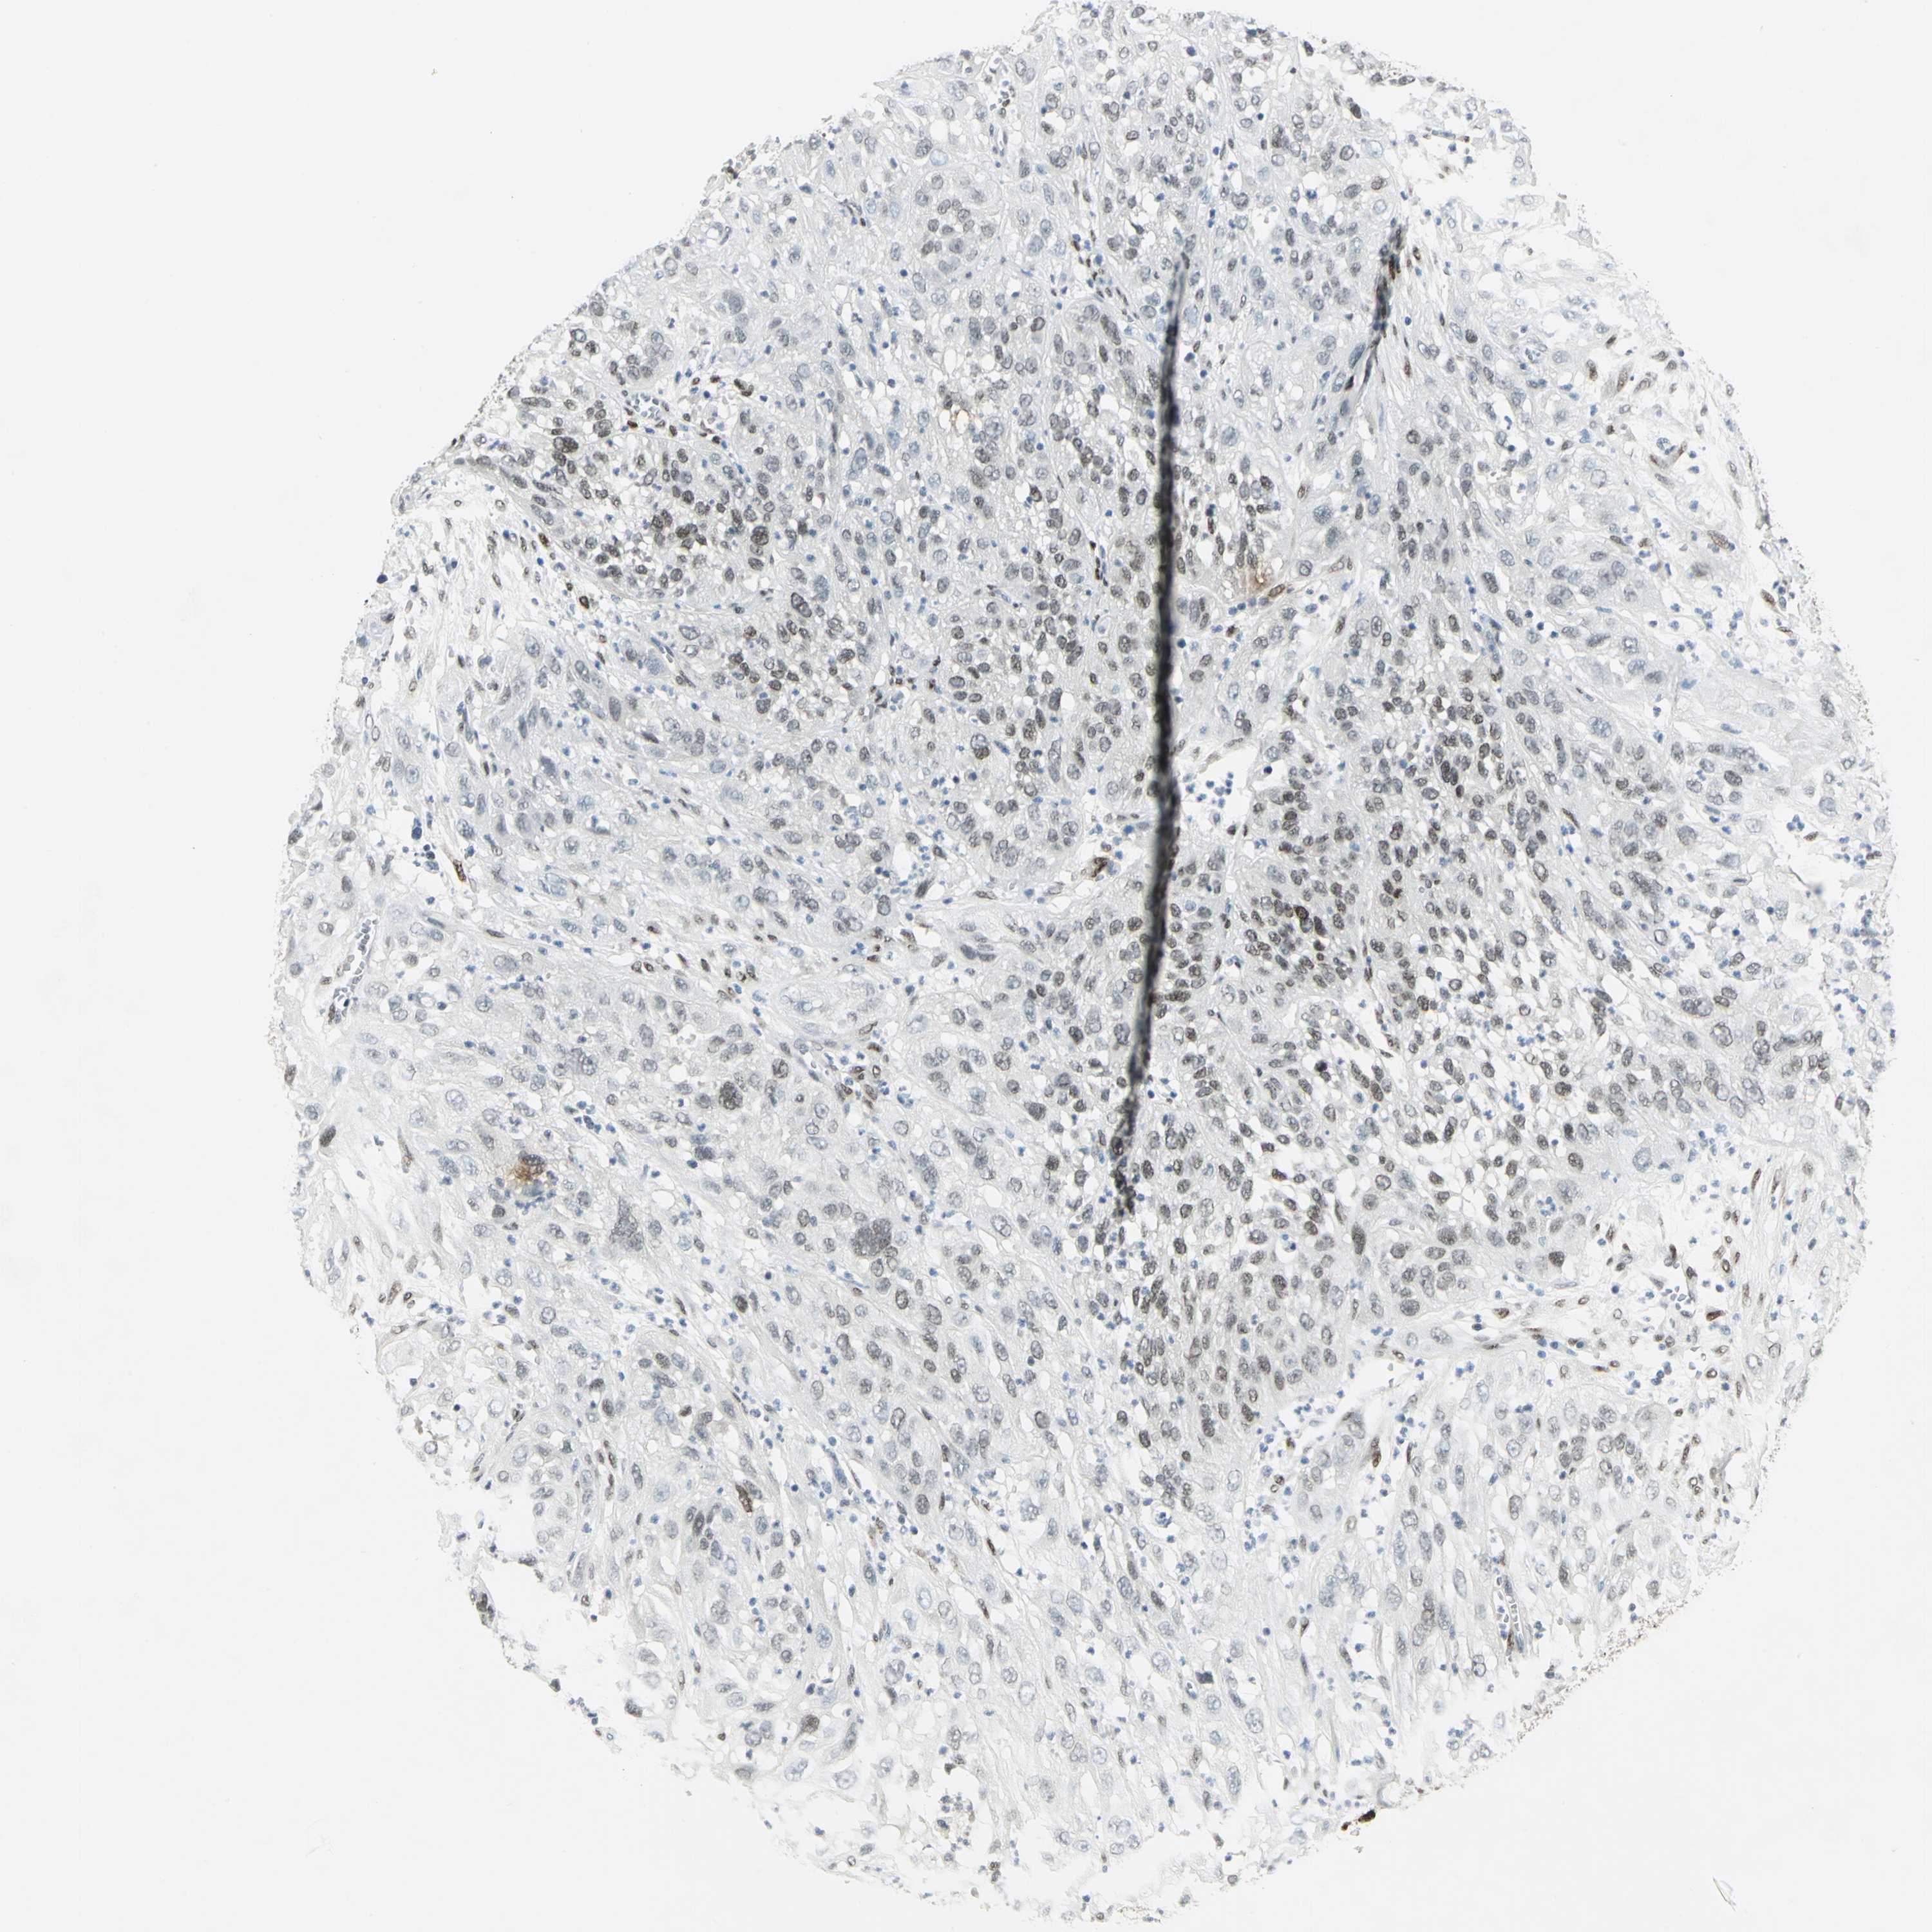

CERVICAL CANCER - Protein expressioni

A mouse-over function shows sample information and annotation data. Click on an image to view it in a full screen mode. Samples can be filtered based on level of antibody staining by selecting one or several of the following categories: high, medium, low and not detected. The assay and annotation is described here.

Note that samples used for immunohistochemistry by the Human Protein Atlas do not correspond to samples in the TCGA dataset.

Antibody stainingi

Antibody staining in the annotated cell types in the current human tissue is reported as not detected, low, medium, or high, based on conventional immunohistochemistry profiling in selected tissues. This score is based on the combination of the staining intensity and fraction of stained cells.

Each image is clickable and will lead to virtual microscopy that enables deeper exploration of all samples and also displays staining intensity scores, fraction scores and subcellular localization as well as patient and tissue information for each sample.

Antibody HPA003256

Antibody CAB004999

Staining

High

Medium

Low

Not detected

Intensity

Strong

Moderate

Weak

Negative

Quantity

>75%

75%-25%

<25%

None

Location

Nuclear

Cytoplasmic/membranous

Cytoplasmic/membranous,nuclear

Squamous cell carcinoma, NOS

Adenocarcinoma, NOS